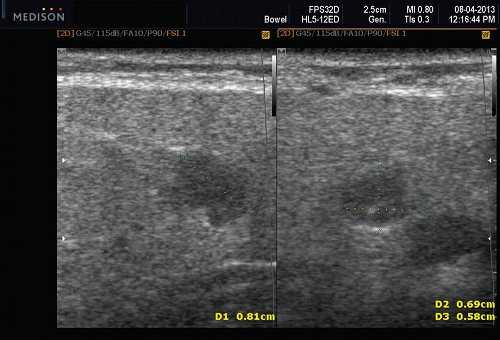

Рис. 5. Камень протока поднижнечелюстной слюнной железы.

Рис. 6. Камень в паренхиме поднижнечелюстной слюнной железы.

Рис. 7. Камень в протоке поднижнечелюстной слюнной железы.

Место расположения. Поднижнечелюстное пространство (ПНП); Камни ПЧЖ можно разделить по местоположению. Дистальный: к отверстию протока в переднем подъязычном пространстве (ППП). Проксимальный: В сторону ворот поднижнечелюстной железы в подчелюстном пространстве. Камни поднижнечелюстной слюнной железы на УЗИ чаще встречаются в протоке, чем в ее паренхиме.

Результаты рентгенографии. Рентгенография. Камни рентгеноконтрастны в 90% серий обычных рентген снимков (окклюзионные виды)